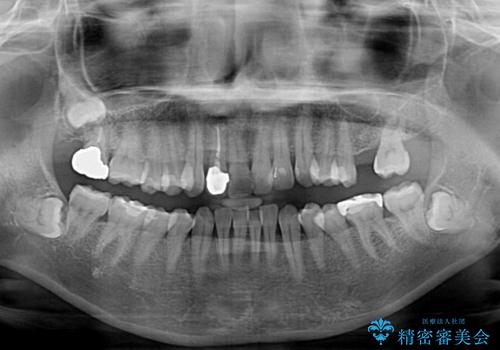

- 前歯のセラミッククラウンの縁が見えることが気になってから、デコボコも気になるようになってきたとのことで来院された患者様です。

デコボコの程度は中等度であったため、インビザライン・モデレートパッケージにて歯列を整えることとしました。

セラミッククラウンの装着されていた前歯と、大きな修復治療の跡がある反対側の歯は、矯正治療後に補綴治療を行うこととしました。

奥歯の欠損はインプラント、ブリッジ、入れ歯のどれにすれば良いかを決められず、仕事が非常にお忙しいこともあり、保留としたまま治療を終えることとなりました。